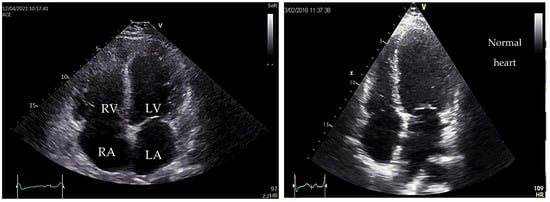

5. Dilated Cardiomyopathy (DCM)